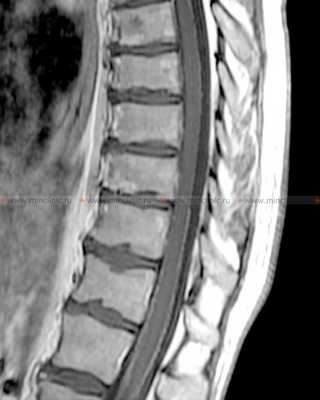

На МРТ спинного мозга после контрастирования визуализируется так называемая "сахарная глазурь" у пациентов с лептоменингеальными метастазами при канцероматозе оболочек мозга.

Люмбальная пункция (ЛП) — это врачебная манипуляция, предназначенная для извлечения спинномозговой жидкости и/или введения в субарахноидальное пространство спинного мозга лекарственных препаратов или контрастных веществ (миелография ).

С диагностической целью люмбальную пункцию проводят для измерения ликворного давления, исследования проходимости субарахноидального пространства спинного мозга, определения цвета, прозрачности и состава спинномозговой жидкости.

По величине давления спинномозговой жидкости в субарахноидальном пространстве спинного мозга можно предположительно судить о внутричерепном давлении (в норме оно составляет 0-200 мм вод.ст.). По изменению давления при ликвородинамических пробах определяют степень проходимости субарахноидального пространства спинного мозга (полная проходимость, частичная блокада, полная блокада).

Люмбальную пункцию проводят для измерения ликворного давления, исследования проходимости субарахноидального пространства спинного мозга, определения цвета, прозрачности и состава спинномозговой жидкости.

Люмбальная пункция позволяет наиболее точно, по сравнению с другими методами, распознать субарахноидальное кровоизлияние и степень его выраженности, выявлять реакции оболочек мозга на черепно-мозговую травму, обнаруживать воспалительные осложнения ЧМТ и травм позвоночника, у больных с карциноматозным менингитом выявлять злокачественные клетки, повышенное содержание белка, снижение концентрации глюкозы.